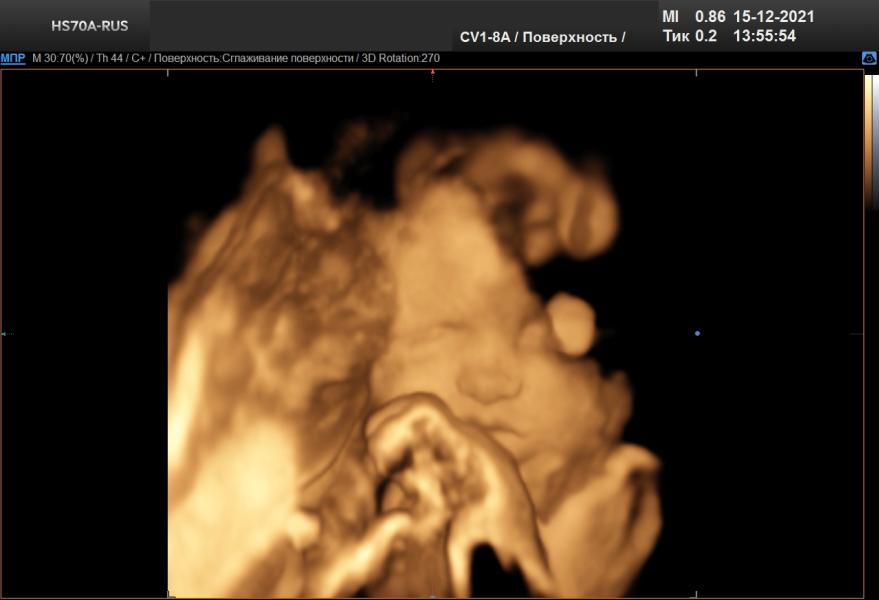

Третий скрининг) 3D) показывала нам язык, хлопала глазками и тянула кулачки в рот))

Наоборот, врач сказала, что на более поздних сроках, чем у меня, дети фиксируются и так сильно не шевелятся как было в моем случае и видно четче